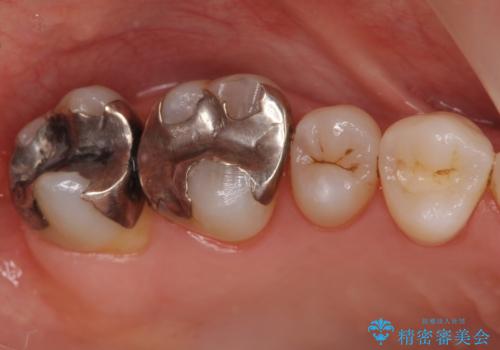

- 症状はないものの、検査の結果右上の奥歯が大きく割れていることが確認されたケースです。

無症状であったため放置していた結果、歯の周囲の骨が溶けてなくなっていました。

歯の深いところまで割れてしまっている場合は健康な状態での歯の保存ができないため抜歯の適応になります。